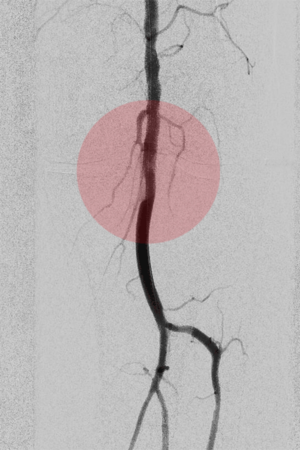

5. Thrombektomie – mechanische Entfernung von Blutgerinnseln

Wenn ein Gefäß durch Blutgerinnsel verschlossen ist, kann man den Verschluss mechanisch wiedereröffnen, indem man die Ablagerungen über spezielle Katheter absaugt. Dazu stehen uns Kathetersysteme, die mit Vakuum arbeiten bzw. zusätzlich die Gerinnsel vor dem Absaugen mit Hilfe von Wasserstrahlen oder Rotation der Katheterspitze zerkleinern, zur Verfügung.